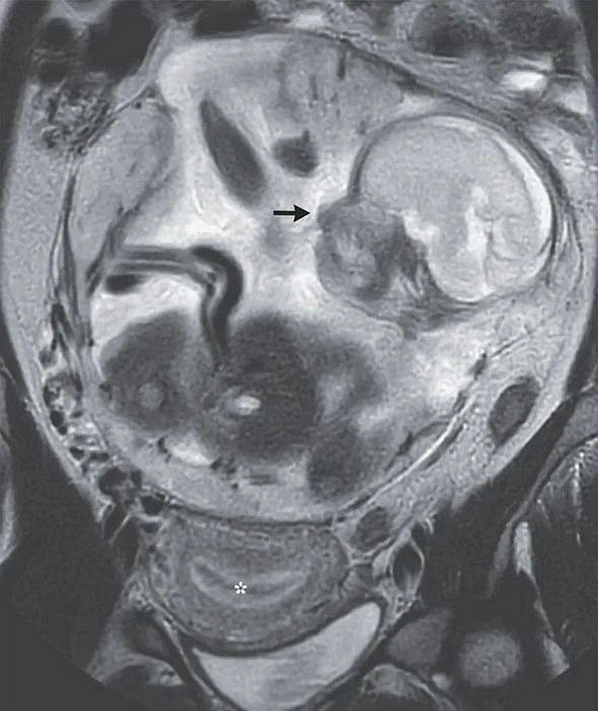

В Соединённых штатах Америки 37-летняя женщина смогла выносить плод вне матки и родить здорового малыша.

Пациентка обратилась в клинику с болями в брюшной полости, но при обследовании медики выявили... беременность. Плод у женщины развивался вне матки уже 23 недели. Ребёнок находился между желудком и кишечником. В медицинской практике обычно в таких случаях выживают лишь 10% малышей, но роженице повезло.

Новорождённый появился на свет на 29-ой неделе беременности методом кесарева сечения. На свет появился недоношенный, но здоровый мальчик.

У женщины это были третьи роды. После операции по извлечению младенца на 25-ый день ей удалили плаценту, которая располагалась в брюшной полости. Спустя два месяца из больницы выписали и малыша.